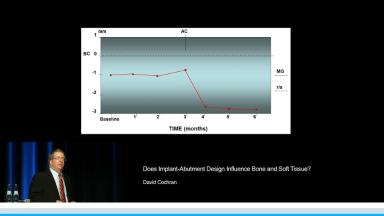

Does Implant-Abutment Design Influence Bone and Soft Tissue?

This lecture presents histomorphometric studies to demonstrate the strong relationship between bone and implant design, especially at the implant-abutment interface. The presenter shares key factors to explain the response of hard and soft tissue at the very first step of osseointegration. He focuses on the interaction between the design of the implant and the bone physiology. He develops the relationship between bone resorption and the inflammatory response of the host. The presenter also discusses different ways to decrease the inflammatory response at the implant-abutment interface. Supported by literature, a complete review of the various implant designs and their interactions with the bone is presented. The three major implant types are discussed: one-piece implant; two-piece implant with butt-joint interface; and two-piece implant with platform switching connection. This is a cutting edge lecture on the bone-implant relationship.

- discuss bone remodeling according to the vertical position of the implant and the location of the abutment interface

- discuss the advantages and disadvantages of the different implant designs in term of hard and soft tissue relationships

- understand the interaction between the bone remodeling process and implant placement